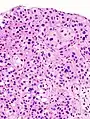

| Histopathology of transitional carcinoma of the urinary bladder. Transurethral biopsy. Hematoxylin and eosin stain. | |

Histopathology of urothelial carcinoma of the urinary bladder, showing a nested pattern of invasion. Transurethral biopsy. Hematoxylin and eosin.